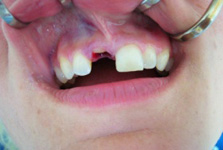

Klasickým příkladem a indikací pro použití implantátu je ztráta jednoho zubu (v tomto případě v předním – frontálním úseku) v jinak zdravém, nepoškozeném chrupu.

Nejčastější příčinou takové ztráty je sportovní nebo dopravní úraz.